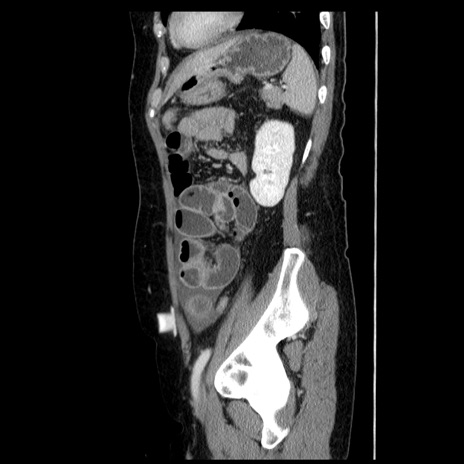

症例6(矢状断像)

【症例】50歳代女性

【主訴】下腹部痛

【既往歴】卵巣癌術後(8年前に当院で卵巣摘出)

【身体所見】 意識清明、腹部:平坦、腸蠕動音→、やや硬、下腹部自発痛・圧痛あり、反跳痛あり、筋性防御なし。

【データ】WBC 16000、CRP 0.01